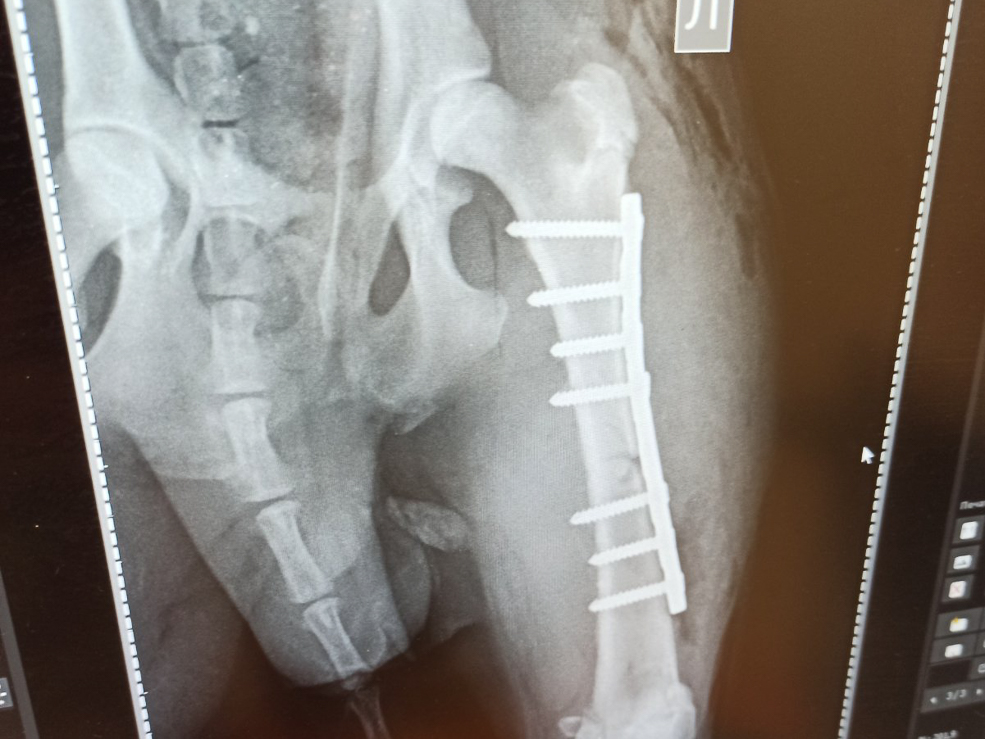

Судя по травмам, самым гуманным решением казалась эвтаназия. Но коллектив вместе с руководством заведения решил, что нельзя так быстро сдаваться и нужно спасть бедолагу, поэтому повезли страдальца в Слуцк на рентген. После проведения обследования было решено, что нужна дорогостоящая операция, которую делают только в Минске.

Коллектив вместе с руководством и родственниками собрали необходимую сумму и сделали операцию, поставив титановую пластину.

– Да, история верна. Он прибился к нам около месяца назад и очаровал всех. Когда с псом случилась беда, подключились моя сестра, коллектив, и все решили, что нужно спасать. Свозили в Слуцк, а потом и в Минск. Сразу сказали, что лечение будет стоить от 400 рублей. В итоге сумма вышла около 800 рублей. Операцию делали в клинике "Девять Жизней". Очень благодарны врачу, который согласился внепланово прооперировать, – поделился собеседник, удивившись, откуда журналисты узнали об этой истории.

Как сказали ветеринары, псу около восьми месяцев, вес - 14 килограммов. Молодой возраст даёт осторожную надежду на то, что с травмой организм справится. Сейчас он в надёжных руках, назвали Гарри.

– Такие пациенты запоминаются особенно, - говорит директор ветклиники Алексей Клянцевич. - Случай оказался не из простых, но с Гарри всё должно быть хорошо - операцию делал один из лучших ветеринарных хирургов страны Андрей Балюк. Радует, когда такие уличные бедолаги встречают неравнодушных людей. В "Девять Жизней" нередко привозят зверушек из Солигорска с тяжёлыми ситуациями, чаще это выставочные породы или питомцы со стажем, так что история действительно не рядовая.

Гарри уже встаёт на лапу, пока что хромает, но на месте ему не сидится. Он продолжает покорять людские сердца своей сообразительностью и любовью к обнимашкам.